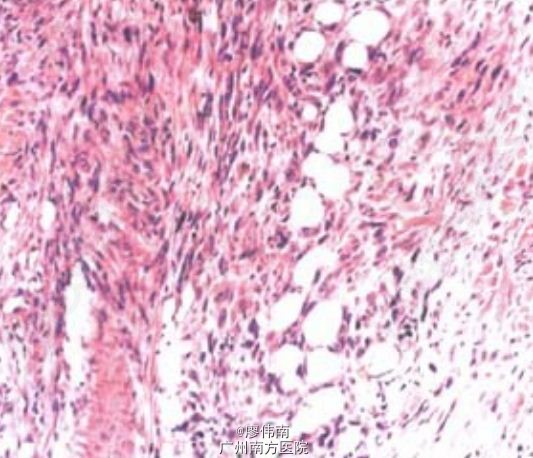

左上肢缺如头皮,鼻背部散在3处花生米至蚕豆大小结节,表面溃疡伴污黑色结痂。组织病理示:胞核不典型,可见有丝分裂。ECT全身骨显像:右颅骨、胸骨、右第3前肋、右侧骶髂关节、右侧髂臼等处可见点状、片状异常核素浓缩影。胸部CT考虑两肺继发性肺结核。

上皮样肉瘤是一种罕见的软组织低度恶性肿瘤,常见于手掌、指屈面及腕部。本病组织学表现有特征性,肿瘤由上皮样或梭形细胞组成多个结节,结节中心多有灶性坏死,呈肉芽肿样。免疫组化方面也有特征性。 本病常反复局部复发,早期即有淋巴结转移,最终可向肺部、胸膜等转移。因此需早期诊断,并作广泛手术切除。若有转移可用化疗。DOI:10.3760/cma.j.issn.0412-4030.2010.01.034